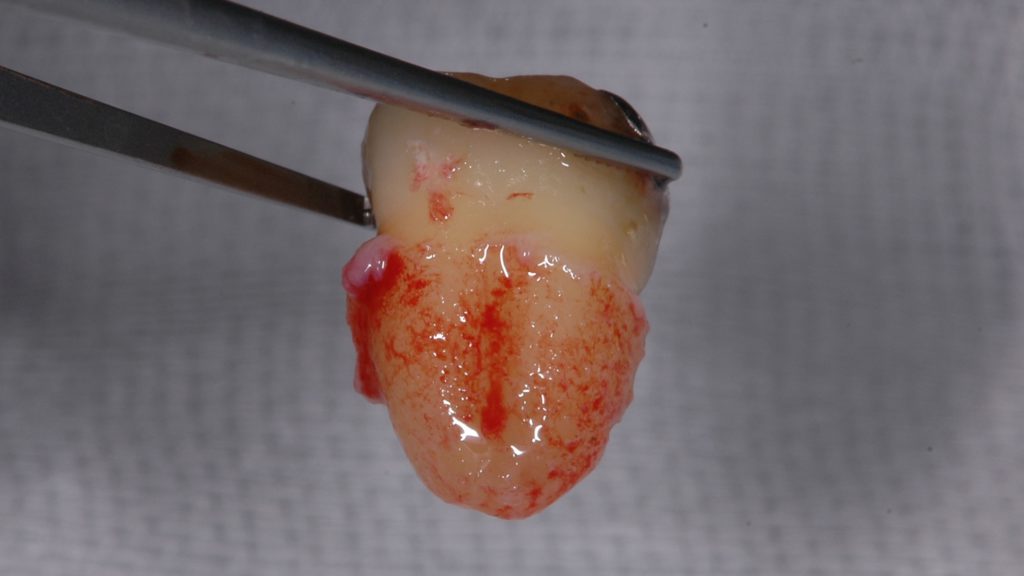

下の写真は親知らずを抜いた直後です。歯の根の周囲に満遍なく歯根膜が残っています。

歯根膜がほぼ完璧に残っている親知らず

下の写真の親知らずでは一部歯根膜がはがれ落ちてしまっているのがわかります。